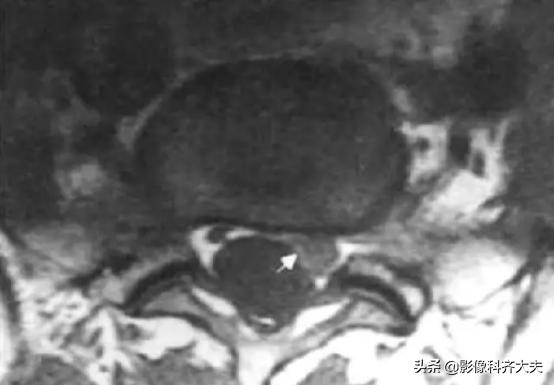

磁共振显示椎间盘突出(外侧型)